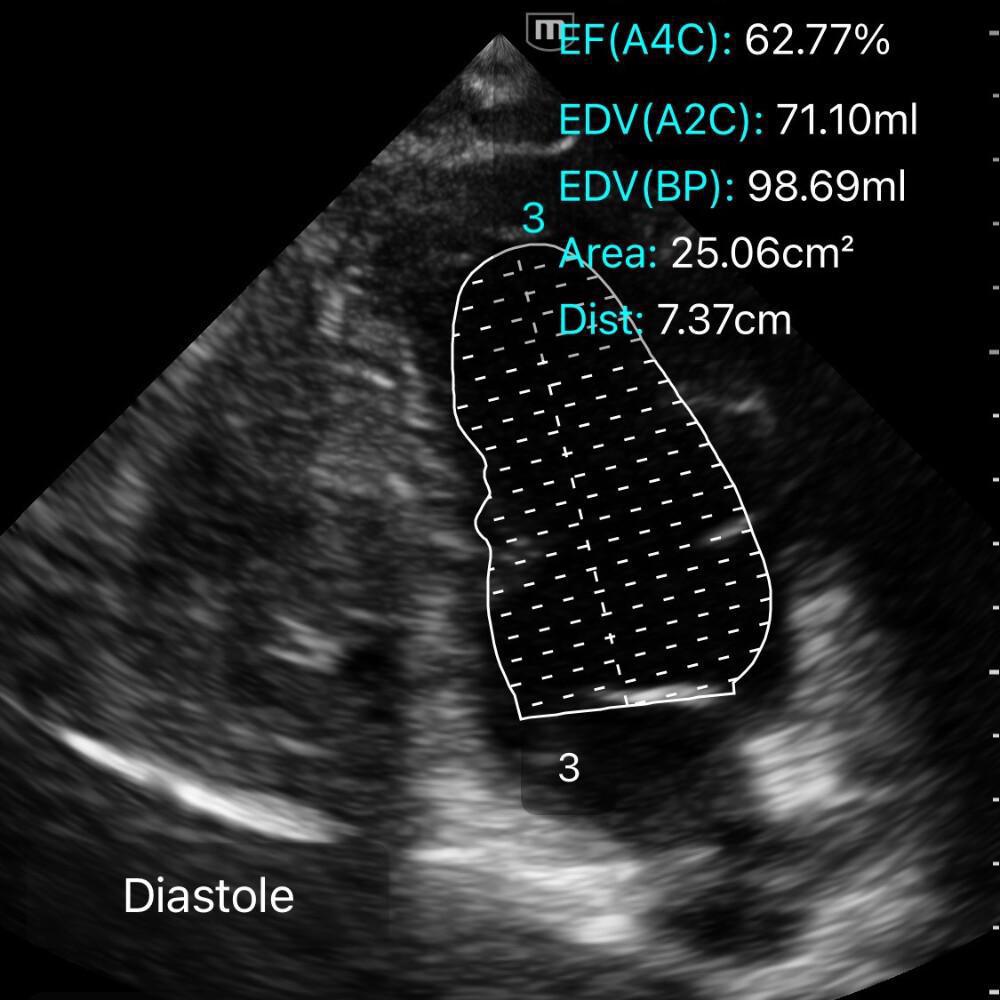

⚡️ Méthode de Simpson biplan

La méthode de Simpson biplan est la référence pour calculer la FEVG en échocardiographie transthoracique.

Elle segmente le VG en multiples coupes dont les volumes sont additionnés pour obtenir le volume télédiastolique (VTD) et le volume télésystolique (VTS).

🧭 Comment réaliser un Simpson biplan

1️⃣ Obtenir deux vues apicales orthogonales

- Apicale 4 cavités

- Apicale 2 cavités

Les deux doivent être strictement non tronqué.

2️⃣ Geler l’image en télédiastole et télésystole

-

Télédiastole = coupe où le VG est le plus large.

Télésystole = coupe où la cavité est la plus petite.

3️⃣ Tracer les contours endocardiques

Dans chaque vue (A4C puis A2C), en télédiastole et télésystole :

Placer les points de repère aux bases des feuillets mitraux.

Suivre précisément le bord endocardique jusqu’à l’apex.

Ne pas inclure les trabéculations ni les muscles papillaires dans la cavité.

➡️ La machine reconstruit ensuite un volume par empilement de coupes.

GIF ci-dessous: tracé du ventricule en diastole/systole (monoplane, démonstratif).

⚠️ Pièges fréquents du Simpson biplan

- Apex raccourci (tronqué): Erreur la plus fréquente. Si l’apex n’est pas parfaitement visible et “pointu”, le VG paraît plus petit → FEVG faussement normale ou élevée.

- Mauvais contour endocardique: Gain trop fort ou trop faible, confusion avec les trabéculations / muscles papillaires → volumes incohérents.

- Mauvais choix de coupes: Télédiastole et télésystole mal identifiées → calcul erroné (souvent ±10–15 % de FEVG).

- Vues non orthogonales (4C / 2C): Si les vues ne sont pas perpendiculaires : reconstruction du VG déformée → VTD/VTS faux.

- Fenêtre acoustique médiocre: Obésité, BPCO, ventilation mécanique, agitation → bords non visibles → méthode inutilisable.

- Temps de réalisation incompatible avec l’état du patient: Méthode lente et opérateur-dépendante : risque d’erreurs si réalisée en conditions instables.